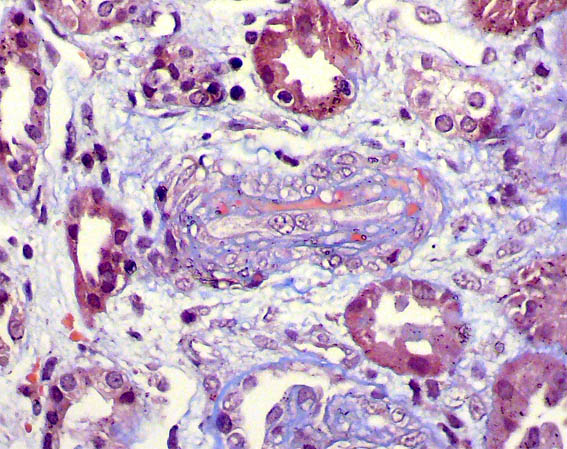

Se hace biopsia renal. Observe las imágenes.

Figura 13. Inmunofluorescencia directa para fibrinógeno, X400.

Figura 14. Inmunofluorescencia directa para fibrinógeno, X400.

Inmunofluorescencia pra IgA, IgG, IgM, C3 y C1q: Negativa.